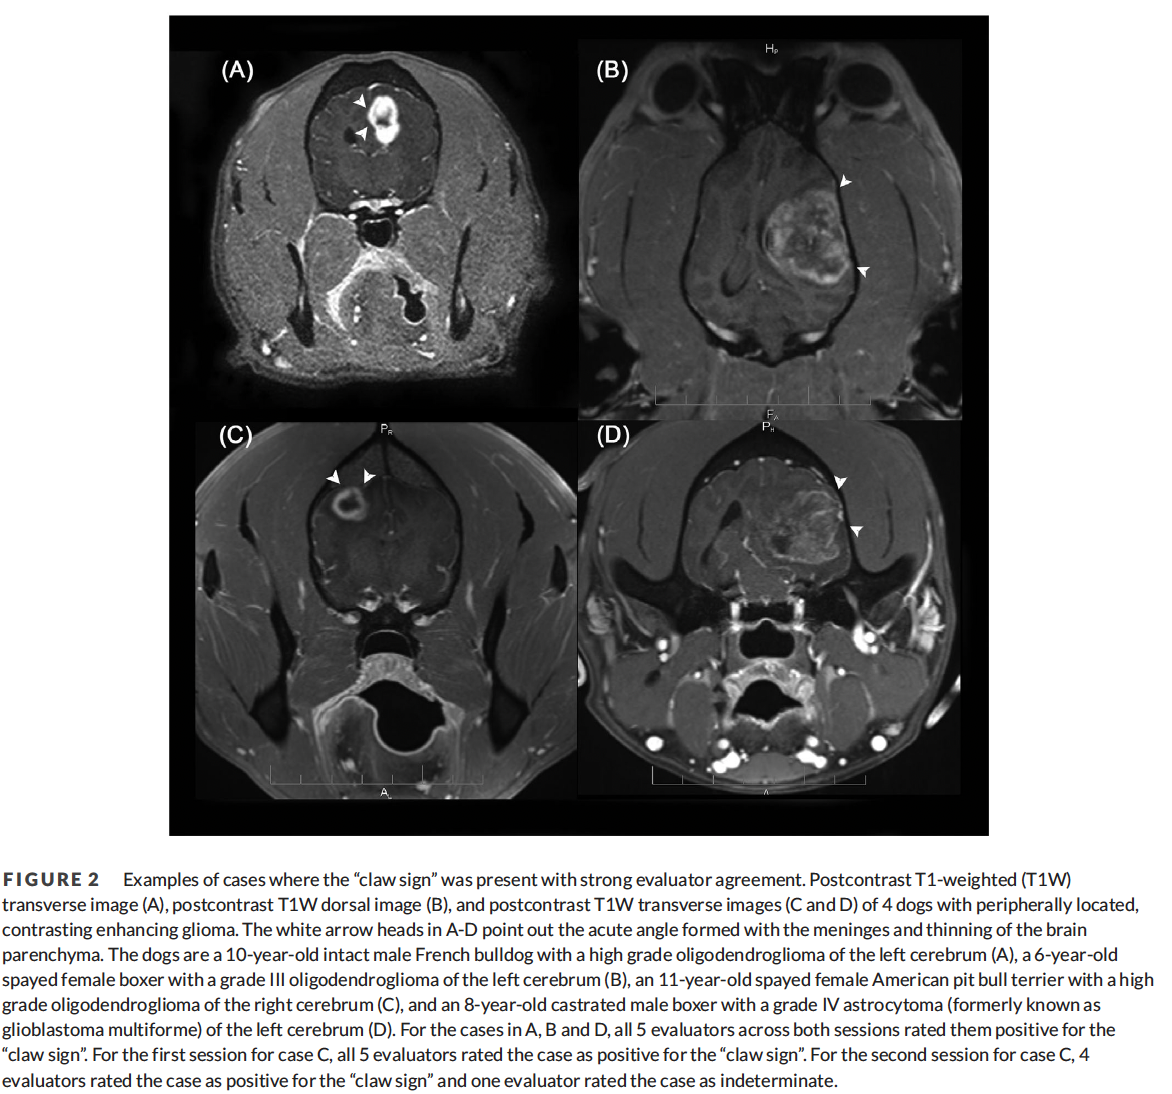

In a study by Glamann 2023 in VRU, what sign on MRI can be used to differentiate between intracranial intra-axial gliomas and extra-axial meningiomas?

A

The claw sign (85% sensitive and 80% specific).